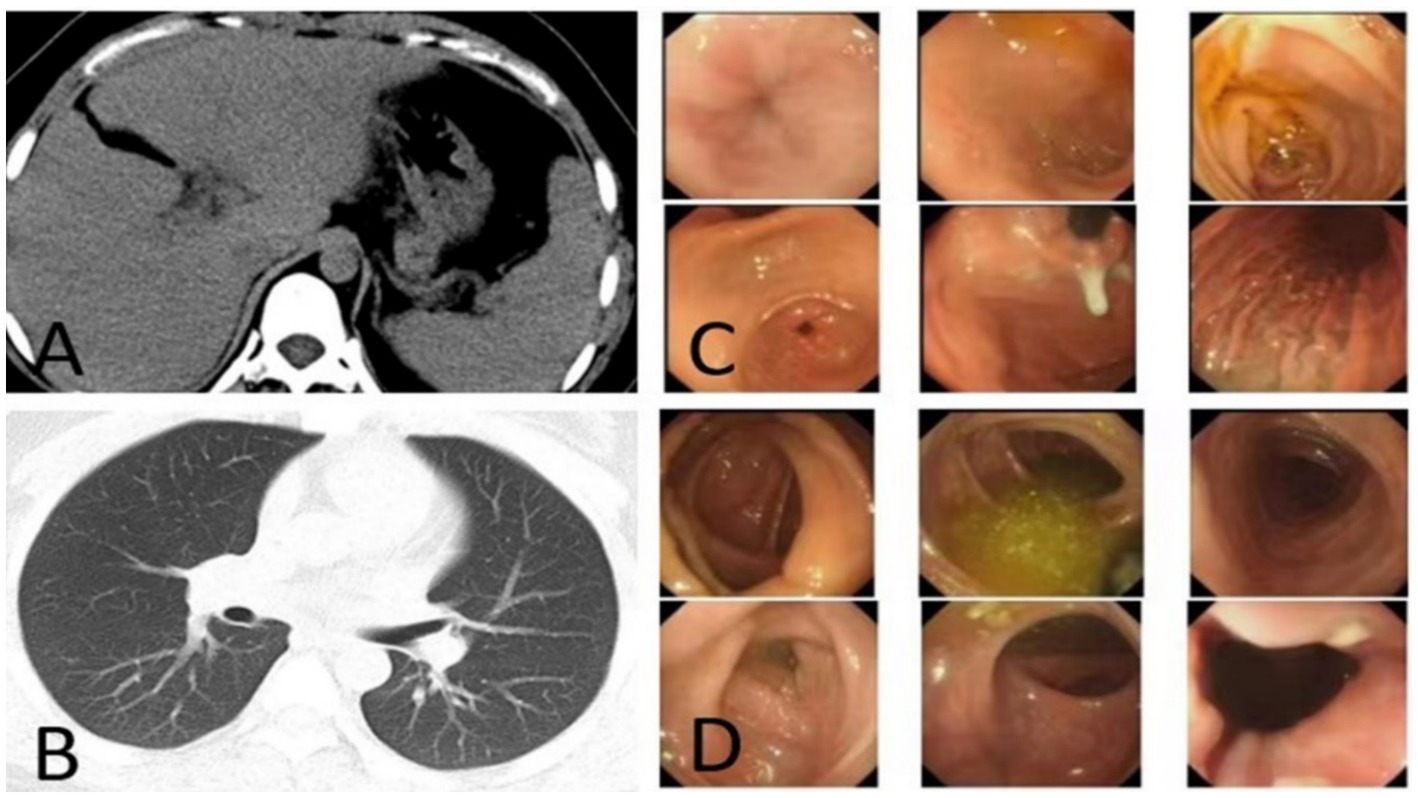

Because the patient is Rh blood type, after a month of blood preparation, she underwent resection of liver segments IV via the right upper abdomen. There was no active bleeding or bile leakage in the operative area. The patient’s vital signs were stable, the operative area pain gradually relieved and the incision recovered well. Histopathology of the resected lesion suggested a neuroendocrine tumor that subtype was hepatic goblet cell adenoid carcinoma. Immunohistological results were positive including chromgranin A (CgA), cluster of differentiation 56 (CD56), cytokeratin (CK)8/18, epithelial membrane antigen (EMA), and Villin (Figures 2A–F). Postoperative abdominal CT images showed that the density of hepatic parenchyma was homogeneous and no residual lesions were found (Figure 3A). The patient had an uneventful recovery after the procedure and underwent further investigation to rule out an extrahepatic origin of the NETs: gastrointestinal endoscopy, colonoscopy, and chest CT scan were negative (Figures 3B–D). And extra-hepatic primary NETs were not found during the two-year follow-up, therefore, the patient was finally diagnosed with PHNETs.

Figure 3

(A) CT image after resection the S4 segment of PHNET, (B–D) first post-operative negative images of chest CT, gastrointestinal endoscopy, and colonoscopy.